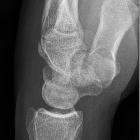

The carpal boss is a hypertrophied bony protuberance on the dorsal surfaces of the base of the second or third metacarpals, near the capitate and trapezium. It may be bilateral.

Radiographic features

The radiographic appearance of a carpal boss is characteristic, however optimal visualization of the boss may be difficult to obtain due to superimposed bony structures.

CT may show degenerative disease at a pseudoarthrosis, and MRI may show edema related to abnormal motion.